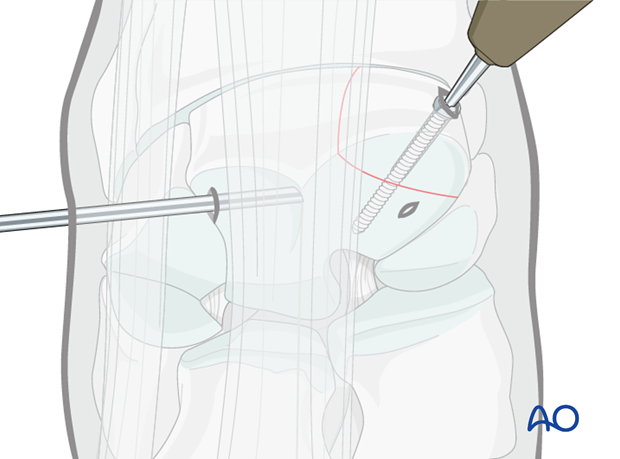

Lag screw insertion is routinely done under arthroscopic control.

The proximal medial and lateral margins of the fracture are defined by arthroscopically guided percutaneous insertion of hypodermic needles.

It is important that these needles are placed perpendicular to the dorsal surface of the carpus to accurately delineate the fracture width.

An 18 gauge spinal needle is subsequently placed midway between these two needles close and parallel to the proximal articular surface and directed across the midpoint of the fracture as close to 90 degrees as possible. This needle is the most important directional guide for implant placement.

The configuration of most frontal plane slab fractures of the radial facet are such that the tip of the needle usually lodges in the palmar fossa of the bone and can be implanted in the non-articular surface to stabilize the spinal needle sufficiently.

Once the spinal needle has been placed, a further 18 gauge needle is inserted parallel to it into the carpometacarpal joint.

Based on the radiographs a stab incision is placed over the dorsal aspect of the third carpal bone half way between the spinal needle and the needle in the carpometacarpal joint.

The glide hole is drilled across the fragment until it enters the fracture line (the distance is predetermined by measurement by the radiographs).

The 3.2 mm drill guide is inserted into the glide hole and the 3.2 mm thread hole is prepared through the remaining third carpal bone.

The 4.5 mm screw of appropriate length is inserted. The screw is tightened under arthroscopic visualization. After the screw is tightened any debris or elevated cartilage is removed from the fracture line.